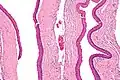

Histologicamente, o QO é caracterizado como uma cavidade cística revestida por uma camada fina de epitélio estratificado escamoso paraqueratinizado, com uma camada basal de células cuboidais ou colunares hipercromáticas em paliçada[4][5]. A queratina na superfície possui um aspecto corrugado característico.[4]

Histologia com ampliação intermediária de um ceratocisto odontogênico. -